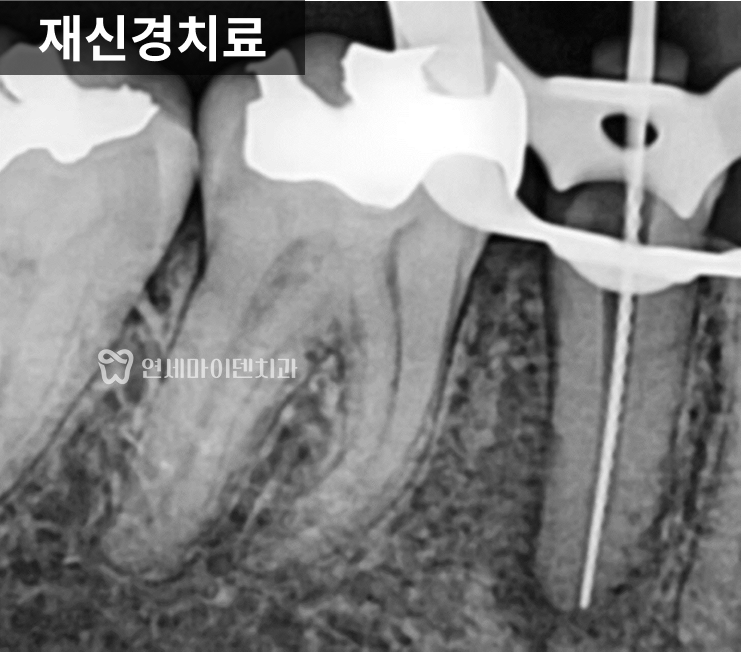

근본적인 치료, 재신경치료 및 회복 과정

치아를 살리기 위해

선택한 방법은 재신경치료였습니다.

미세현미경을 이용해 이전 신경치료에선

닿지 않았던 뿌리 끝까지 깨끗하게 소독하고,

내부를 철저히 청소한 뒤 밀폐했습니다.